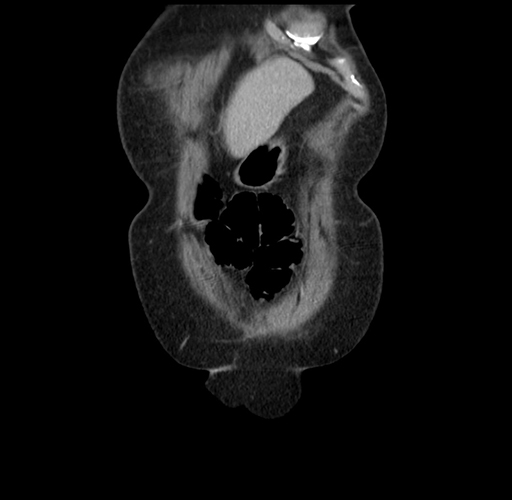

MRI T1